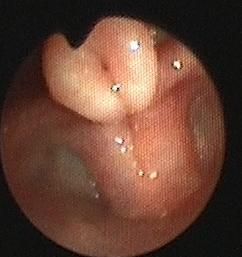

卷曲的会厌软骨遮挡声门 正常会厌软骨及声门

慢性间歇性发作的婴幼儿喉喘呜最常见的病因是喉软化,一般发生于生后数周出现,1岁左右自愈。但是如果婴幼儿出现慢性持续性加重性喉鸣,需要进行颈部、肺部增强CT及气道重建检查、心脏彩超、电子喉镜及支气管镜等检查辅助检查以明确是否存在咽喉部囊肿、血管瘤及声门下狭窄等疾病。